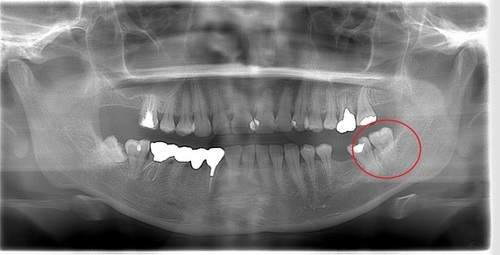

右下奥歯が痛い症例

- 抜歯前写真(レントゲン)

- 抜去歯の写真(CT画像)

| 年齢 | 40代・男性 |

|---|---|

| 主訴 | 右下奥歯が痛い |

| 親知らずの生え方 | 斜めに生えている |

| 抜歯時間 | 30分 |

| 費用 | 約6,000円(保険診療、CT代含む) |

| 抜歯内容 | レントゲン上で右下の親知らずが大きく虫歯になっており、斜めに生えていることもあり患者様の希望により抜歯することとなりました。 当日は痛みがあったため抗生剤と鎮痛剤にて炎症を抑え、後日歯ぐきを切開し、抜歯を行いました。 レントゲン上でも分かるように親知らずの根が二つに分かれており根が折れてしまう可能性がありましたが、このケースでは事前にCTを撮影し、歯の位置、根の方向を確認していたため根が折れることなく抜歯ができました。 術後数日は腫れと痛みがありましたが、薬の服用で抑えることができ、1週間後の糸取りの際には痛み、腫れともになくなっていました。 |